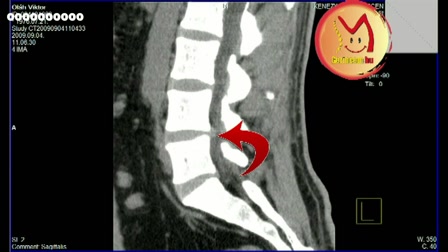

Gerincbarát tornák gerincsérvvel okosan

Gerincbarát tornák gerincsérvvel okosan. www.gerincem.hu